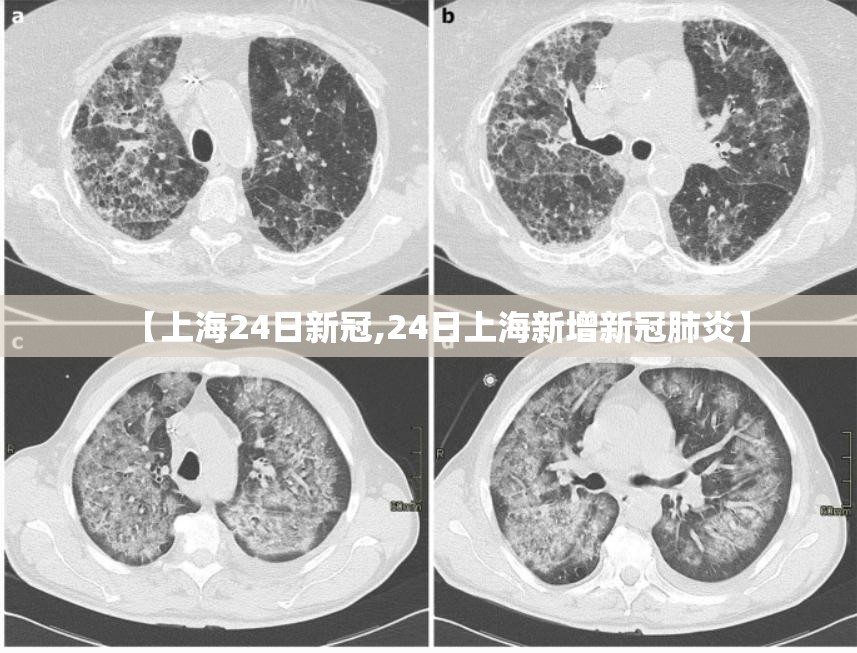

2022年,对于上海而言,是刻骨铭心的一年,在这一年的众多时间节点中,“上海24日新冠”并非特指某一个月,而是成为了一个反复出现的、具有特定意义的符号,它可能指向三月、四月某个关键的24日,那是全域静态管理的决策日或一个疫情数据的高峰日;也可能指向后续月份中,某个宣布重大调整或阶段性成果的24日,无论具体指向哪一天,“上海24日新冠”这个组合,都为我们观察这座超大型城市在极限压力下的应对、挣扎、坚守与复苏,提供了一个极具代表性的时间切片,它不仅仅是一个日期和事件的记录,更是一面镜子,映照出城市的治理能力、社会的人情冷暖以及个体在时代洪流中的命运沉浮。